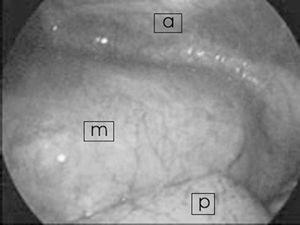

Varón de 14 años que en las 24 h previas a su ingreso presenta un dolor torácico agudo con disnea que aumenta con el decúbito supino. Previamente a este episodio había estado asintomático. En la exploración lo único destacable fue un soplo II/VI. En la radiografía de tórax se vio ensanchamiento mediastínico, sugerente de masa en mediastino anterior, motivo por el cual se decidió ingreso y realización de tomografía computarizada (TC) torácica urgente (fig. 1). En este estudio se observa una masa de 12×13×18 cm mediastínica anterior, en región prevascular, de característica sólida, heterogénea y acompañada de un derrame pleural izquierdo de escasa cantidad. Los estudios de laboratorio, hemograma y marcadores tumorales (α -fetoproteína y β -gonadotropina coriónica humana) fueron normales. Se realiza estudio cardiológico en el que lo único objetivable es una leve obstrucción a la salida del ventrículo derecho. Ante estos hallazgos se decidió biopsia tumoral y estudio de la médula ósea. El diagnóstico anatomopatológico dio como primera posibilidad teratoma quístico maduro, sin poder descartar quiste tímico multilocular. La médula ósea fue normal. Bajo anestesia general, se realizó toracoscopia colocando al paciente en decúbito lateral derecho. No se realizó intubación selectiva. Se emplearon 4 trócares de 5 mm y una óptica de 30°. No se encontraron adherencias pleurales, el colapso del pulmón se consiguió mediante neumotórax controlado de 8-10 mmHg, sin que éste provocara alteraciones gasométricas. La posterior retracción del pulmón dejó ver una tumoración de gran tamaño que ocupaba el compartimiento anterior del mediastino en vecindad con el pericardio (fig. 2). El tumor se encontraba adherido a la pared anterior torácica sobre la zona de la biopsia previa, pero no se observó invasión de los tejidos adyacentes. Se comenzó la disección de la tumoración por su porción más basal separándola del pericardio sin dañar éste, evitando el sangrado mediante el empleo de un dispositivo de sellado de vasos (ligasure). La disección se completó hasta su conexión extratorácica con el tejido tímico. La masa se introdujo en una bolsa de laparoscopia y se extrajo ampliando una de las incisiones de los trócares. Se colocó un tubo de drenaje endotorácico que se retiró a los 2 días. El postoperatorio trascurrió sin complicaciones y fue dado de alta asintomático. La pieza se diagnosticó de teratoma quístico maduro. En revisiones posteriores el paciente presentó buen estado general, heridas de buen aspecto y sin recidivas tras año y medio.

Figura 2. Imagen toracoscópica de la tumoración y su relación con el pulmón. A: pared torácica anterior; P: pulmón; M: masa mediastino anterior.